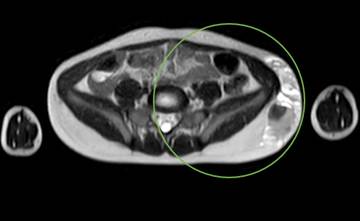

Infante de ocho años, llevado al servicio de urgencias por masa abdominal dolorosa de un año de evolución, localizada en el flanco izquierdo. Al examen físico se encontró una masa violácea, firme y dolorosa en el flanco izquierdo, sobre la cresta ilíaca, de aproximadamente 8x4 cm. La ecografía abdominal informó una lesión quística multiseptada versus estructuras cilíndricas vasculares dilatadas de 13x3,2x2,1 cm, sin flujo Doppler en su interior, sin componente sólido (Figura 2). En la resonancia nuclear magnética (RNM) se encontró una masa que deformaba la pared del flanco izquierdo y la pelvis izquierda, con septos intermedios, probablemente relacionado con hematomas (Figura 3). Se consideró malformación de bajo flujo, posiblemente linfática, y se le realizó manejo percutáneo con agentes esclerosantes (bleomicina 15 UI) (Figura 4), siendo dado de alta, con reingreso al mes por dolor abdominal y vómito. Una nueva ecografía abdominal informó hallazgos similares a los iniciales, además de cambios inflamatorios adyacentes. Se realizó manejo únicamente con antiinflamatorio no esteroideo con resolución de los síntomas. Posteriormente no se logró realizar seguimiento del paciente.